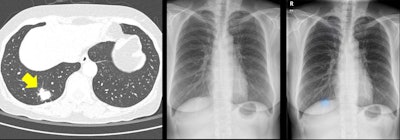

Left: Image of a 64-year-old woman with confirmed lung adenocarcinoma at the right lower lobe (arrow). Center: The lesion, located at the right retrodiaphragmatic area, was missed during routine clinical practice. Right: In the reader performance test, none of the thoracic radiologists detected the lesion. The algorithm successfully localized the lesion (light blue shaded area) with a probability score of 0.16. Caption and images courtesy of the RSNA.Although their performance improved after using the algorithm, the radiologists could not reach the model's standalone performance level, according to the authors. The readers were likely to miss retrocardiac and retrodiaphragmatic nodules. At lower lung fields, they also neglected more true nodules, regarding them as nipple or vascular shadow, the researchers noted.

"Because the algorithm takes pixel values of the image, it may recognize abnormalities in areas of soft-tissue density better than do human readers," they wrote. "In addition, readers accepted larger nodules and showed limited acceptance rate for subcentimeter nodules."